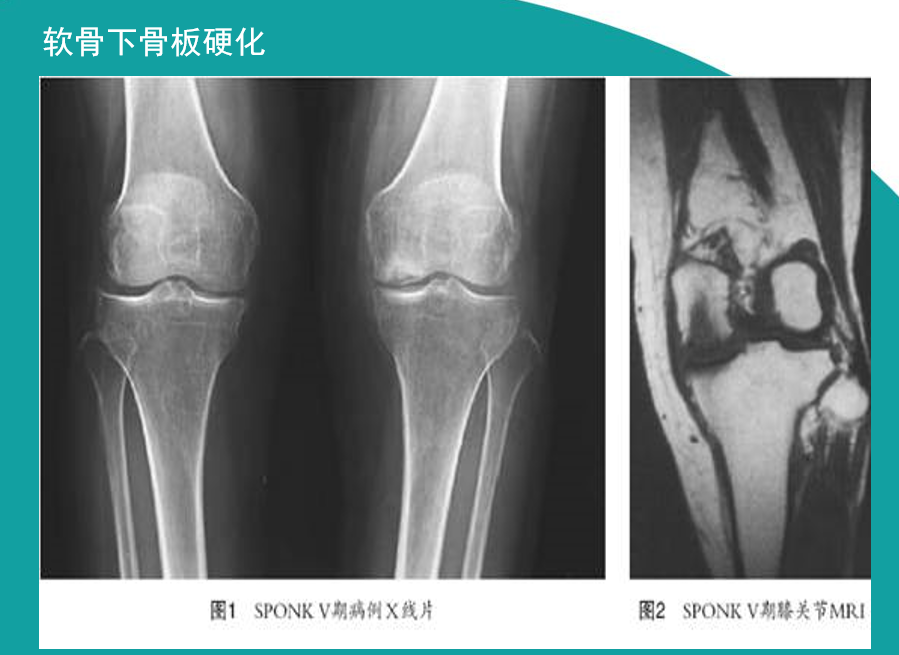

影像学检查方法

X线检查基本特征1.关节间隙变窄:成人膝关节间隙为4mm,小于3mm即为关节间隙狭窄,60岁以上的老人膝关节间隙为3mm,小于2mm为关节间隙狭窄。2.软骨下骨板硬化:软骨下骨板致密、硬化,负重软骨下骨质内可见囊性改变。3.骨赘形成

关节软骨的改变:软骨水肿、软骨囊性变、软骨变薄、磨损、软骨破坏